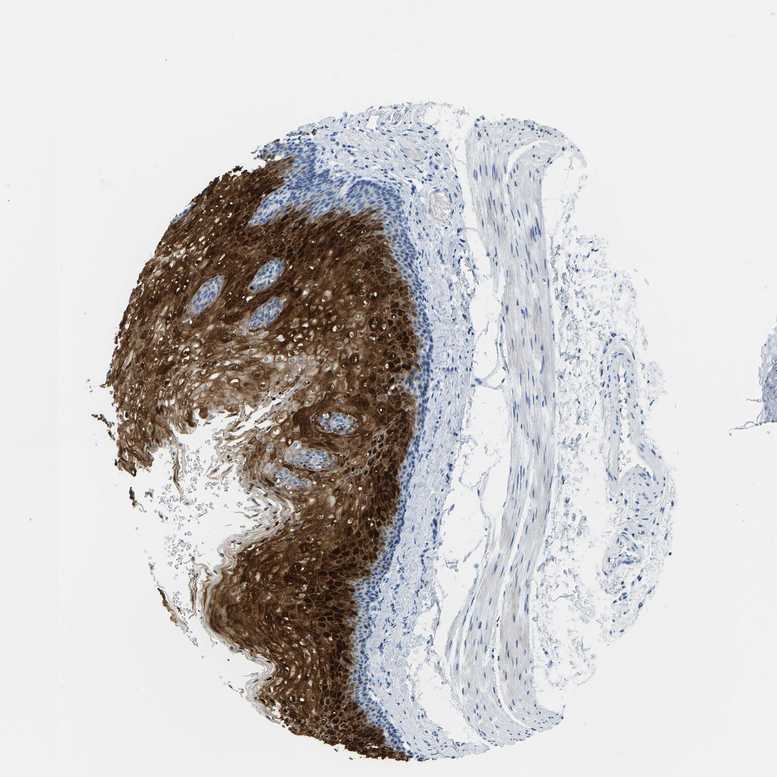

ESOPHAGUS - Antibody stainingi

Antibody staining in the annotated cell types in the current human tissue is reported as not detected, low, medium, or high, based on conventional immunohistochemistry profiling in selected tissues. This score is based on the combination of the staining intensity and fraction of stained cells.

Each image is clickable and will lead to virtual microscopy that enables deeper exploration of all samples and also displays staining intensity scores, fraction scores and subcellular localization as well as patient and tissue information for each sample.

Antibody HPA048341Antibody HPA049988Antibody HPA055992Antibody CAB018772Antibody CAB036007

Squamous epithelial cells MediumMediumMediumHighHigh